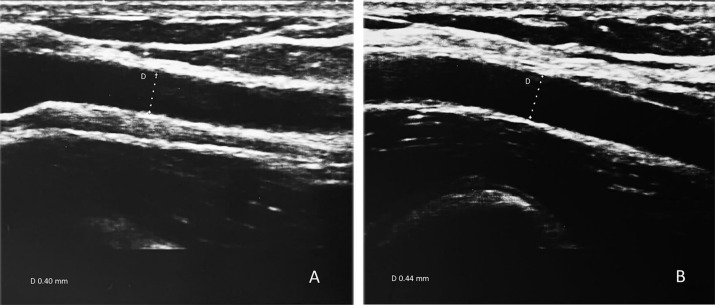

Brachial artery flow-mediated dilation (FMD%)

Fig. 1.

A Baseline brachial artery diameter before the occlusion. B Average brachial artery diameter after reactive hyperemia (FMD % value-10%)